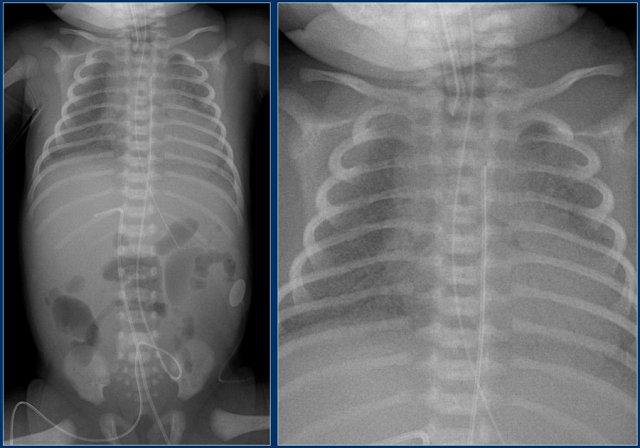

- Đường truyền tĩnh mạch rốn quá sâu, đầu catheter đang nằm trong nhĩ phải.

- Đường truyền động mạch rốn ở mức T10 (vị trí lý tưởng là từ T6 đến T9).

- Ống nội khí quản được đặt quá sâu.

Đầu ống cần nằm cách chỗ phân đôi khí quản 1 cm về phía trên.

- Đường truyền tĩnh mạch rốn quá sâu.

- Sau khi điều chỉnh lại, đầu catheter ở vị trí phù hợp.

Lưu ý rằng ống nội khí quản vẫn còn đặt quá sâu.